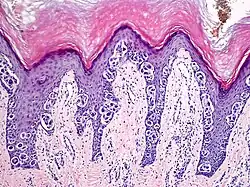

An acral nevus is a cutaneous condition of the palms, soles, fingers, or toes (peripheral body parts), characterized by a skin lesion that is usually macular or only slightly elevated, and may display a uniform brown or dark brown color, often with linear striations.[1]: 1726